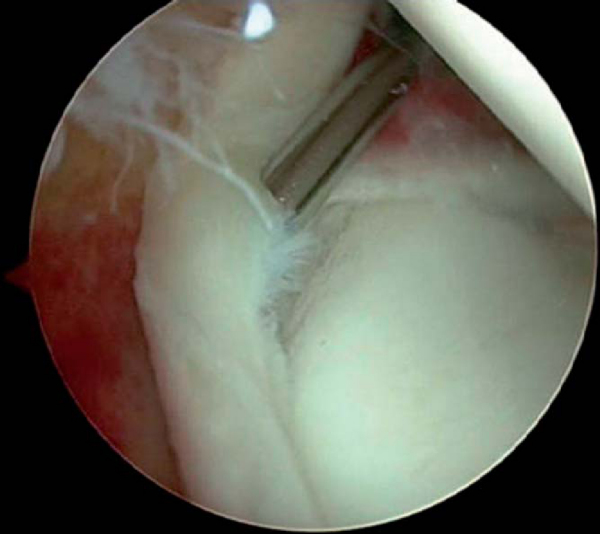

The peel-back test is performed by removing the arm from traction and placing it into the abducted and externally rotated position. With a posterior SLAP lesion, the labrum can be observed to fall medially along the glenoid neck during this maneuver (

Fig. 10-6

). Anterior SLAP lesions will have a negative result of the peel-back test. After assessment of the biceps anchor, the probe is used to assess the undersurface of the rotator cuff and to estimate depth of partial-thickness tears, to determine the stability of the anterior inferior labrum, and to identify any redundancy in the anterior capsule.[3]